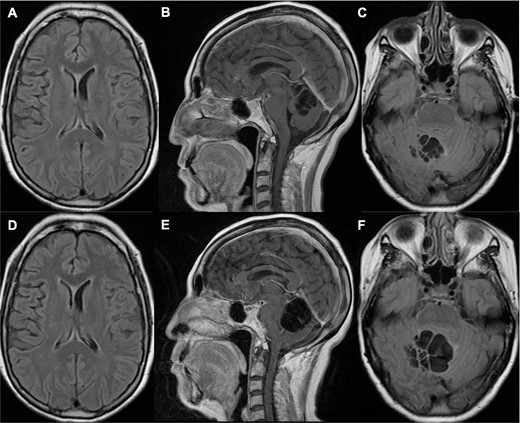

A 66-year-old woman presented with ataxia and dysmetria. She had a past medical history of hydrocephalus and seizures secondary to neurocysticercosis that merited medical management with a 30-day protocol of albendazole administration at 15 mg/kg/d and placement of a ventriculoperitoneal shunt (Fig. 1). Over the year before admission, brain imaging revealed multiple and increasing cystic lesions in the right cerebellar hemisphere (Fig. 2A–C). Besides, a follow-up brain MRI with contrast revealed multiple contrast-enhancing cysts compressing the fourth ventricle, perilesional edema, and an extra ventricular component next to the cerebellar tentorium (Fig. 2D–F).

Brain MRI one year (A–C) and 14 months (D–F) prior to her current admission. (A–B) T1 sequence depicted multiple cystic lesions in the cerebellum without significant compression of the fourth ventricle; (C) T2 fluid-attenuated inversion recovery (FLAIR) sequence showed slight perilesional edema; (D–E) T1 sequence demonstrated a notable increase in cyst growth along with compression of the fourth ventricle; (F) T2 FLAIR sequence showed increased edema.